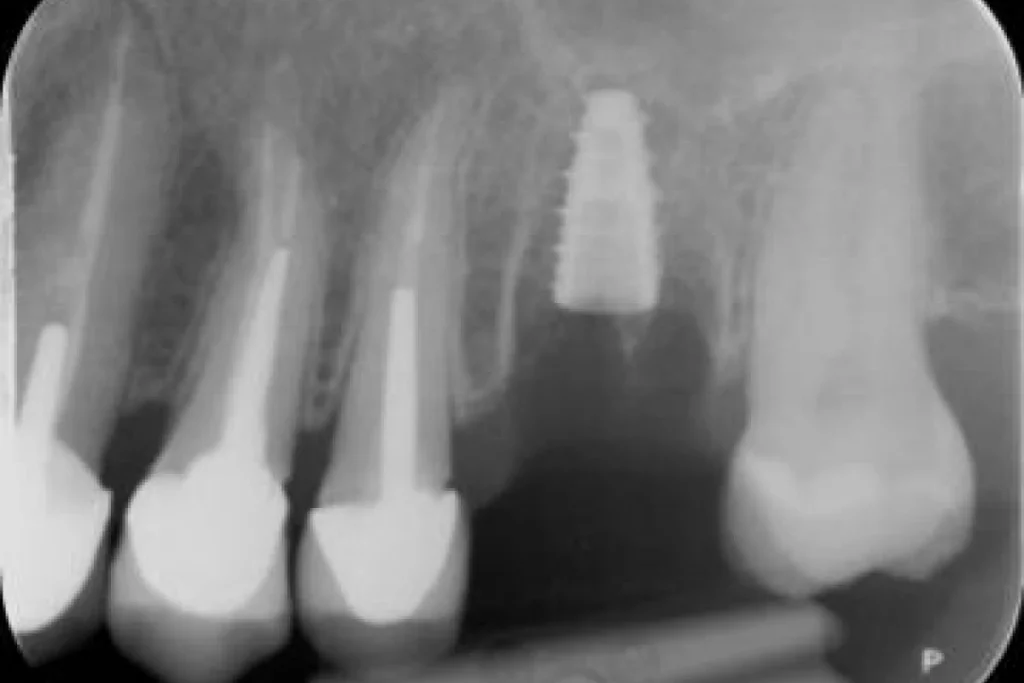

Nous vous présentons le cas de Mme B. 53 ans, qui consulte suite à des douleurs sur sa molaire supérieure gauche.

Après un examen clinique et radiographique, le verdict tombe… la dent n’est malheureusement plus conservable.

Après lui avoir exposé les différentes solutions, Madame B. souhaite remplacer sa dent par un implant. C’est la solution de choix pour retrouver une dent fixe sans avoir à abimer les dents de part et d’autre. L’analyse du scanner nous permet de proposer à Madame B. une extraction implantation immédiate. Il s’agit de réaliser en une seule et même séance l’extraction de la dent condamnée et la mise en place de l’implant dentaire.

Cela permet d’éviter une 2ème chirurgie à notre patiente et de raccourcir la durée du traitement de plusieurs mois. Un comblement osseux est réalisé le jour de l’intervention.

3 mois après la pose de l’implant, la patiente peut retrouver une dent fonctionnelle et esthétique.